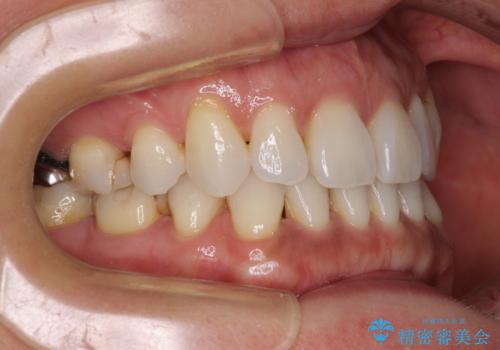

抜歯矯正の後戻りをインビザライン・ライトで解消

- 下顎前歯を中心に、以前行った矯正治療の後戻りが気になるとのことで来院された患者様です。

後戻りは軽度であったため、インビザライン・ライトにて治療を行うこととしました。

矯正治療後は、再度後戻りすることを極力回避するために、下顎前歯の舌側を細いワイヤーを用いて保定することとしました。